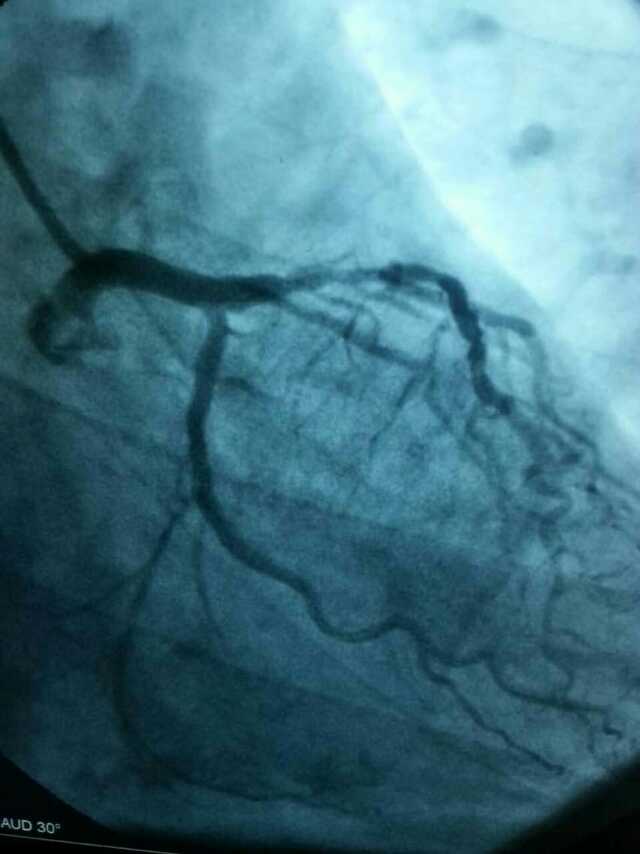

3月20日,家住翔安的庄先生为感谢跳蛋视频 心血管内科的医护人员在第一时间对他的病情给予明确诊断,并及时采取有效治疗措施,让他的心脏病很快得到康复回家。特地送来一面写着“德医双馨,妙手回春”锦旗以表达他们满满的感激之情。